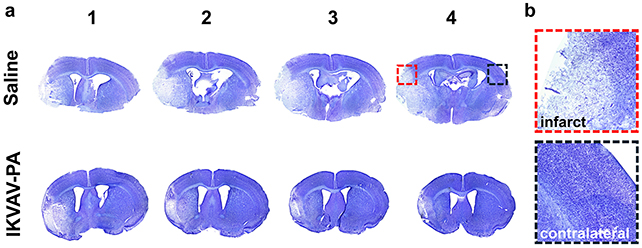

During the experimental phase with mice, the initial objective was successfully achieved: facilitating the compound’s entry into the brain via the bloodstream. Furthermore, adverse reactions and widespread systemic disruption appeared to be negligible, suggesting the therapy effectively targeted the infarction site.

In comparison to control subjects that did not receive the intervention, mice administered the injectable biomaterial subsequent to the restoration of cerebral circulation displayed reduced neural tissue impairment, attenuated inflammatory markers, and a decrease in detrimental immunological responses.